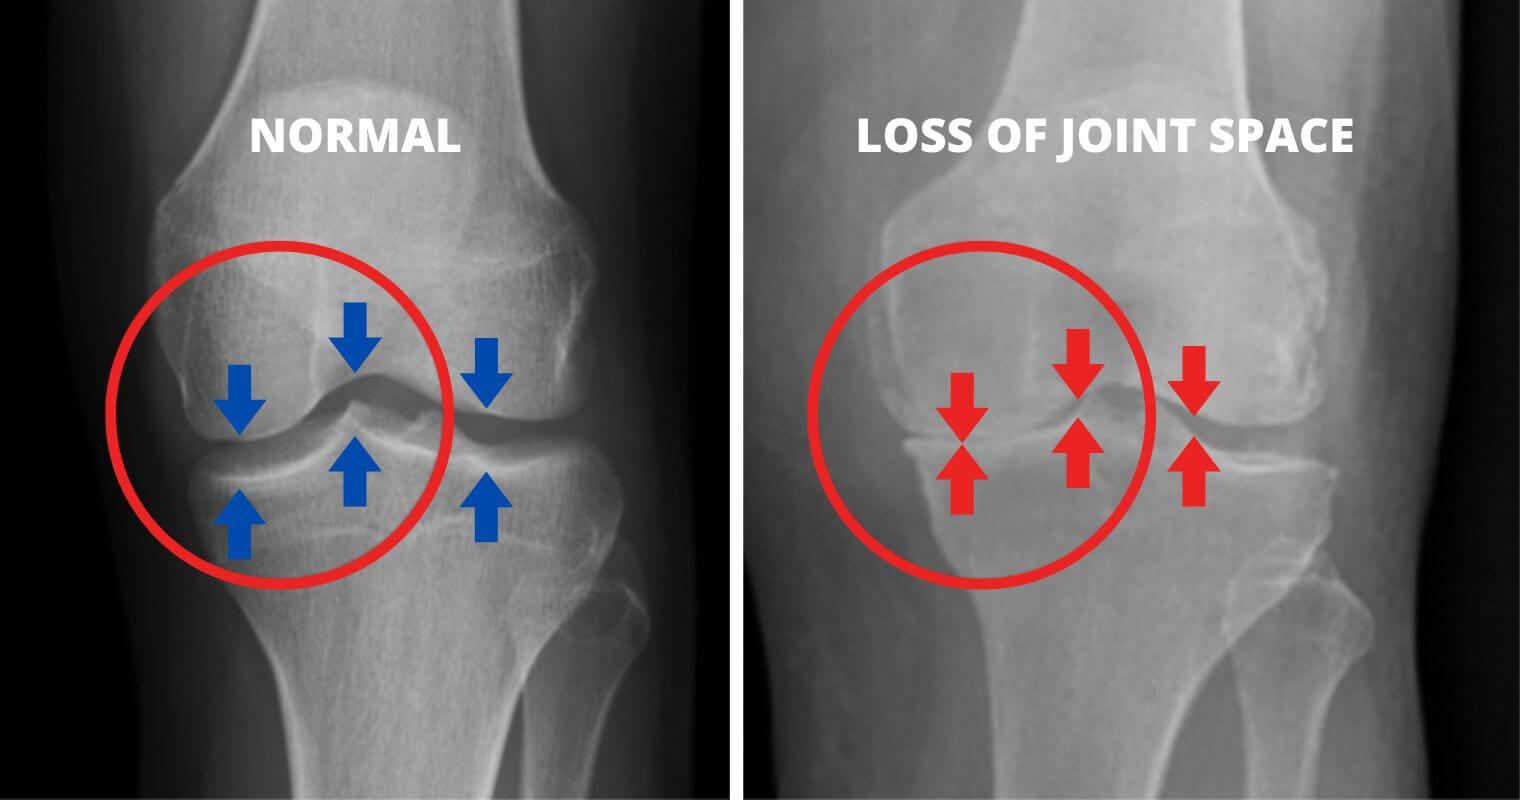

What if I told you that the knee pain and stiffness you feel are caused by the wear and tear of your cartilage, leading to bone-on-bone friction?

As the cartilage wears away over time, the bones start to rub against each other, causing intense pain and discomfort. This friction leads to discomfort, swelling, and a significant reduction in mobility.

As you age and continue to put stress on your knees, the cartilage deteriorates. And when this happens, you start experiencing severe pain due to the bones rubbing together.